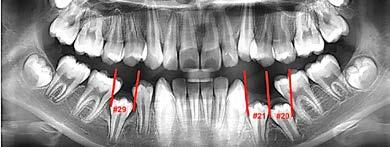

Estudios radiográficos iniciales

En la radiografía lateral de cráneo se ve el diagnósitico: clase II esqueléti ca, con crecimiento hiperdivergente, mordida profunda anterior (Figura 4).

En la radiografía panorámica se observa 28 piezas dentales, con un diastema en los incisivos centrales (Figura 5).

Estudios radiográficos de inicio en la radiografía lateral de cráneo (Figu ra 5) tenemos la clase II esquelética con un ANB de 7°, hiperdivergencia, aumento de la altura facial anterior, disminución de la altura facial poste rior y proclinación del incisivo supe rior con 1 a plano palatino de 121° e incisivo inferior de 1 a plano mandi bular de 99°.

En la radiografía panorámica (Figu ra 6) se observan 32 dientes, con los terceros molares en formación, adicionalmente la molar 46 con una

Figura 6. Radiografía panorámica inicio.

Corrección de mordida abierta anterior por deglución atípica Figura 5. Radiografía lateral de cráneo inicio.